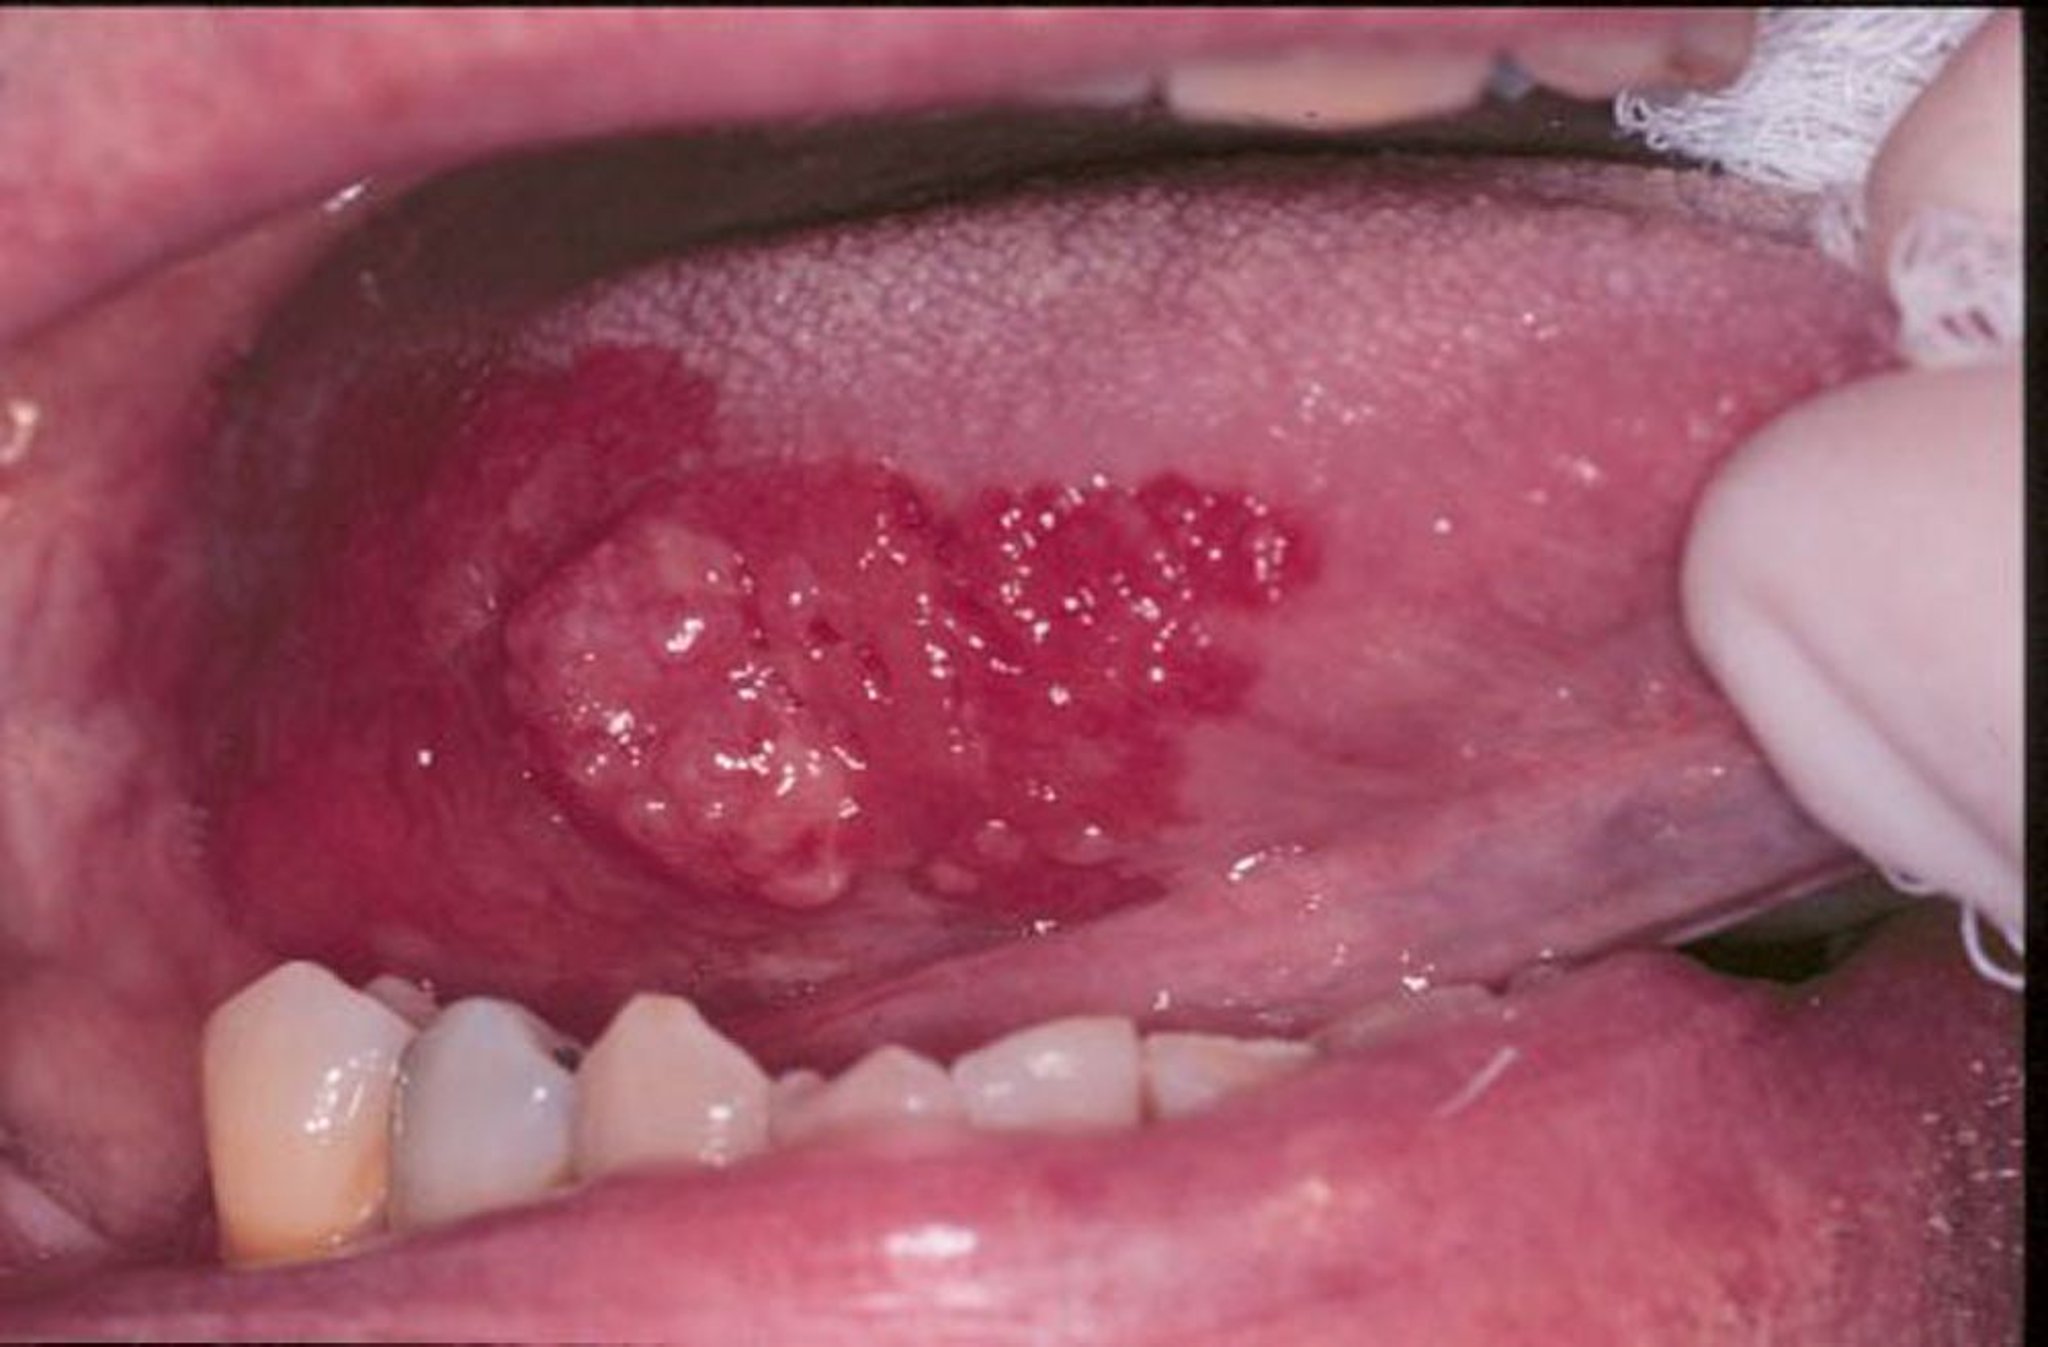

Erythroplasie und Plattenepithelkarzinom

Erythroplasie ist ein Sammelbegriff für rote, flache oder wie abgenutzter Samt aussehende Wunden, die sich im Mund entwickeln. In diesem Bild ist ein Plattenepithelkarzinom von einer Erythroplasie umgeben.

Abbildung mit Genehmigung von Dr. med. dent. Jonathan A. Ship.